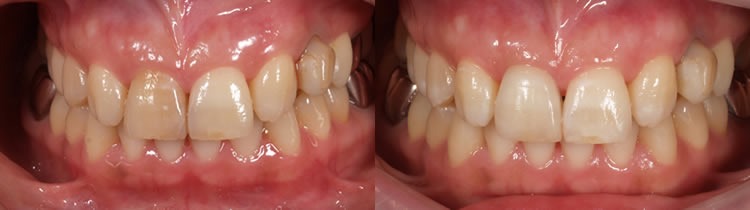

ファイナルレストレーション